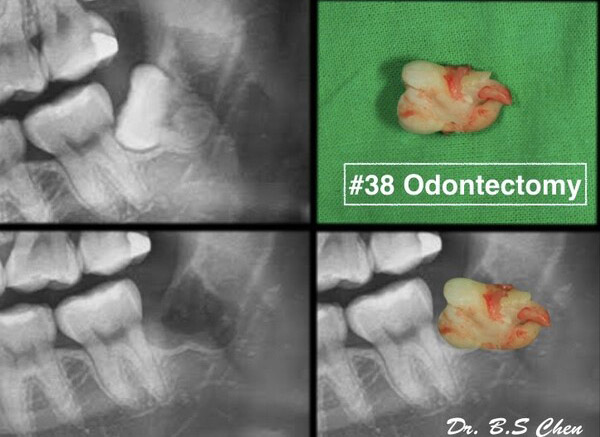

微創智齒手術案例分享